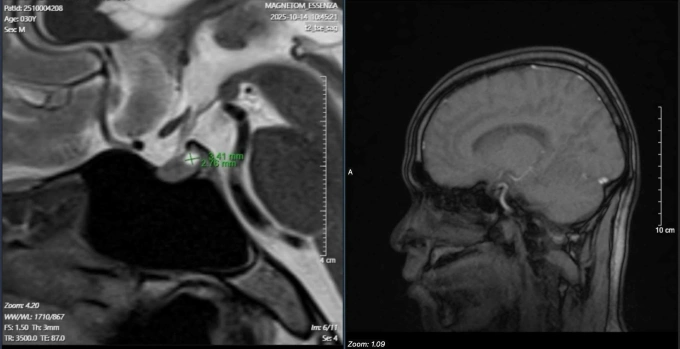

Kết quả xét nghiệm thấy nồng độ hormone prolactin trong máu tăng cao bất thường – dấu hiệu tuyến yên đang bị rối loạn hoạt động. Dựa trên kinh nghiệm lâm sàng, bác sĩ Lực tư vấn chụp MRI tuyến yên, kết quả xác nhận bệnh nhân có u tuyến yên. Khối u lành tính nằm ngay vùng não nhưng đang “khống chế” toàn bộ hệ sinh dục, gây tăng tiết hormone prolactin, ức chế trục nội tiết quan trọng, dẫn đến suy giảm ham muốn và rối loạn cương dai dẳng.

Bệnh nhân được chuyển sang khoa Phẫu thuật Thần kinh để tiếp tục điều trị khối u tuyến yên, đồng thời bổ sung testosterone ngoại sinh nhằm khôi phục lại chức năng sinh dục bị suy giảm.